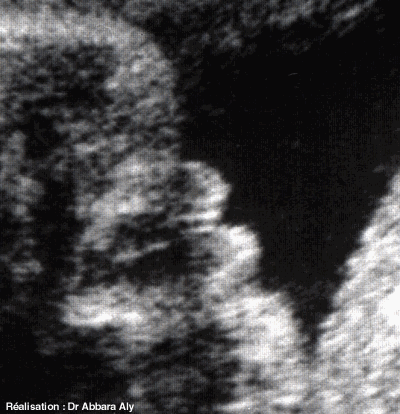

Échographie fœtale : sexe féminin (coupe frontale)

33 SA